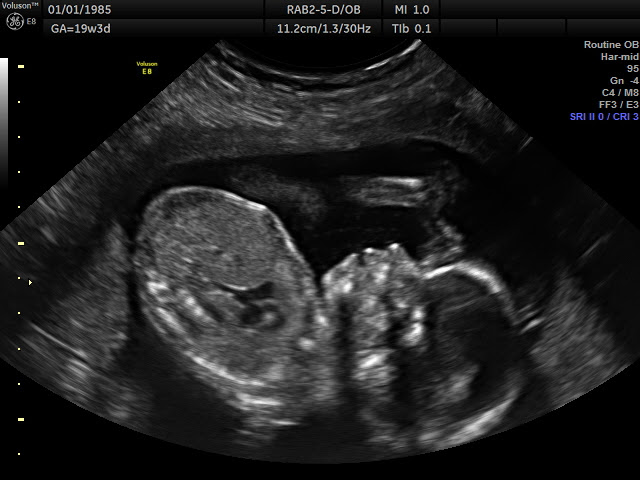

Well, as many of you know, we had our 20 week ultrasound of baby Frazier 2.0 on 28DEC15. What a special day that was! First and foremost, we found out that 2.0 will be another little girl! Boy did we surprise a lot of people! By the end of the tally we had 24 votes for a girl, and 35 votes for a boy!! The fun thing about doing the tallies is I have saved them for both this baby, and Novella, and they have been saved in their pregnancy journals along with ultrasound photos. When I was due with Novella, my mom passed down her pregnancy journal and my baby journal to me, I plan to do the same, as I try to document all that I can, so hopefully one day when they are bringing my grand babies (God willing) into this world that they can look back and see what it was like for their momma when carrying them! So it is a fun journey for me to document. So although I have not been actively blogging, I am still writing, so I cannot complain!

Onto the rest of our doctor appointment. Baby Girl 2.0 looks very healthy, and good. According to ultrasound photos she has a different forehead from Novella, but the same sweet mouth and lips. It is wild how much you can see and learn from ultrasounds these days! She however has a expected due date of 20MAY16, but is measuring to be due 21MAY16, which oddly enough is the day BEFORE Novellas second birthday! People joked and said maybe they would share birthdays, God only knows and it will be revealed to us in a few short months! The day of our ultrasound as we drove back from Green Bay, it began to snow, that night it snowed 13 inches in less than 12 hours with high winds that left snow drifts in our driveway up to four feet high! Talk about an extremely memorable day and night!